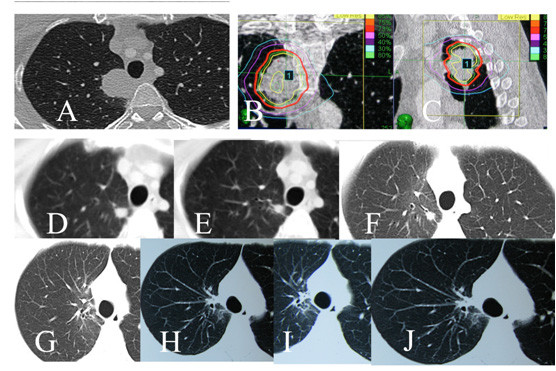

5、神经系统以外肿瘤的射波刀治疗:射波刀除了治疗神经系统肿瘤和血管畸形外,目前它主要应用于全身肿瘤的放射外科治疗。根据文献报道,射波刀治疗的多数病例为神经系统以外的肿瘤。射波刀已广泛用于肺癌(如图11)、肝脏肿瘤、肾脏肿瘤、前列腺癌、骨肿瘤和一些妇科肿瘤的放射治疗。

图11:晚期肺腺癌患者,因脑部转移瘤行开颅手术,病理诊断为腺癌,肺CT检查发现肺癌,然后射波刀治疗。A、B和C:射波刀治疗前肺部CT, A为水平位,B: 为冠状位,C:为矢状位,图像中的红色曲线为治疗时的等剂量曲线。照射3次,每天1次,每次12Gy。DE:治疗后2月,肿瘤缩小为小的结节。FG: 治疗后5个月,肿瘤几乎消失;HIJ: 治疗后7个月,肿瘤消失。